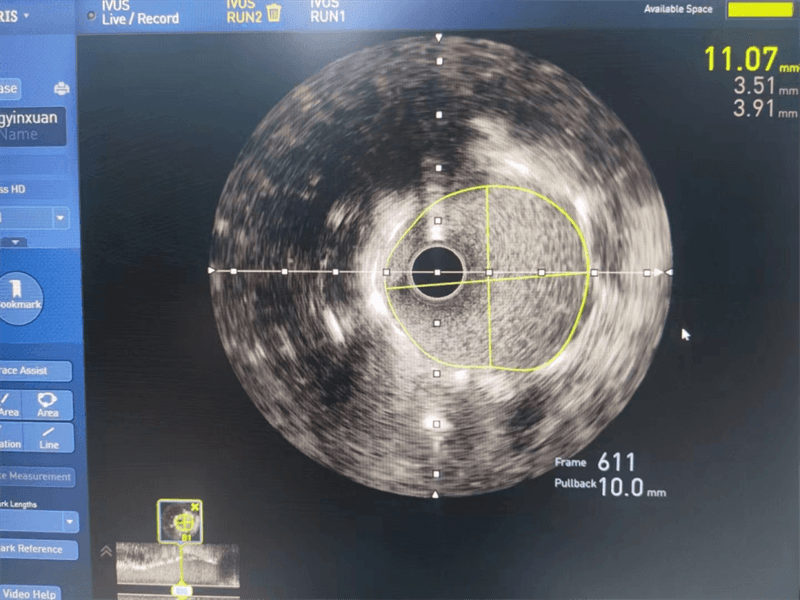

與患者家屬溝通后,其女兒猶豫不決、憂心忡忡,經過崔主任認真分析病情、充分溝通,征得患者及家屬同意后,為安全、精準處理病變,選擇進行血管內超聲檢查,經血管內超聲檢查提示左主干至前降支近段纖維斑塊,球囊擴張后面積3.97mm2,斑塊負荷70%,回旋支近段中度狹窄,斑塊負荷較輕。

我們結合患者病變特點,對回旋支支架內閉塞病變處藥物球囊治療,左主干病變植入1枚支架,術后,造影顯示左主干病變處支架植入狀態良好,血管內超聲顯示支架貼壁良好,患者血壓、心率穩定,癥狀完全緩解,并安全返回重癥監護室進一步治療,術后張大伯無明顯不適,生命體征穩定,病情明顯好轉。